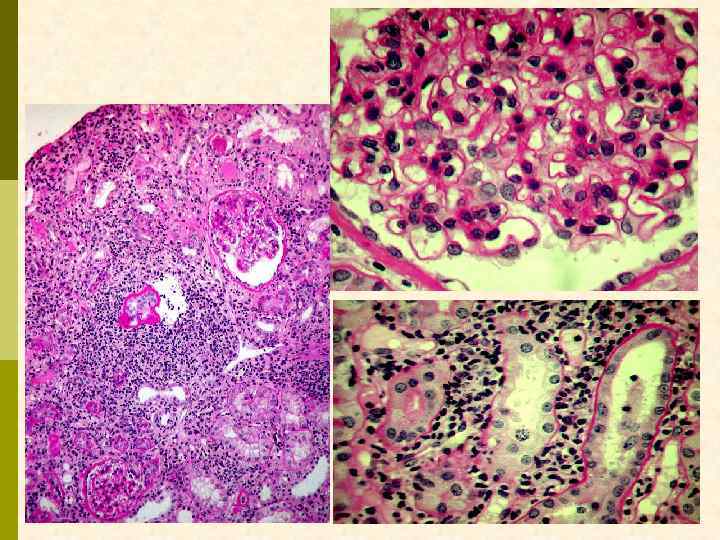

Характерные морфологические признаки ВИЧАН p почки больших размеров p тяжелое повреждение клубочков – коллаптоидный вариант ФСГС p расширение мезангия p гиперплазия и пролиферация подоцитов, аномалия висцерального и париетального эпителия клубочков – дедифференцирование ? ? ? p иммунные депозиты минимальны p атрофия канальцевого эпителия, кистозная дегенерация канальцев с заполнением их белковыми цилиндрами p нередкий тяжелый интерстициальный отек с моноцитарной (лимфоцитарной) инфильтрацией p нередко острый канальцевый некроз p ЭМ: тубуло-ретикулярные структуры в эндотелиоцитах клубочковых капилляров и других сосудов

Характерные морфологические признаки ВИЧ-ассоциированной нефропатии Фокальный сегментарный гломерулосклероз, коллаптоидный вариант.

Характерные морфологические признаки ВИЧ-ассоциированной нефропатии Фокальный сегментарный гломерулосклероз (длинная стрелка) с коллапсом клубочка (короткая стрелка), микрокистозные изменения канальцев (звёздочки), лимфоцитарная инфильтрация интерстиция, интерстициальный фиброз (PАS-реакция). Ross MJ, Klotman PE. AIDS 2004, Vol 18 No 8